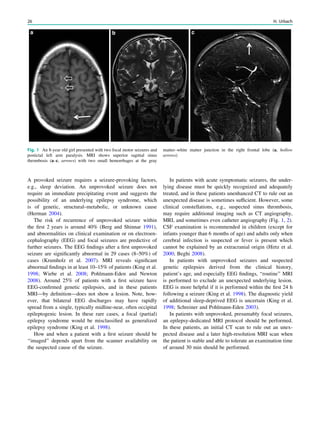

Fig. 1 An 8-year old girl presented with two focal motor seizures and

postictal left arm paralysis. MRI shows superior sagittal sinus

thrombosis (a–c, arrows) with two small hemorrhages at the gray

matter–white matter junction in the right frontal lobe (a, hollow

arrows)